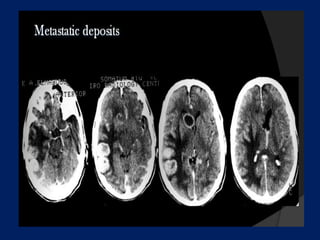

Presentation1.pptx, supratentorial brain tumour